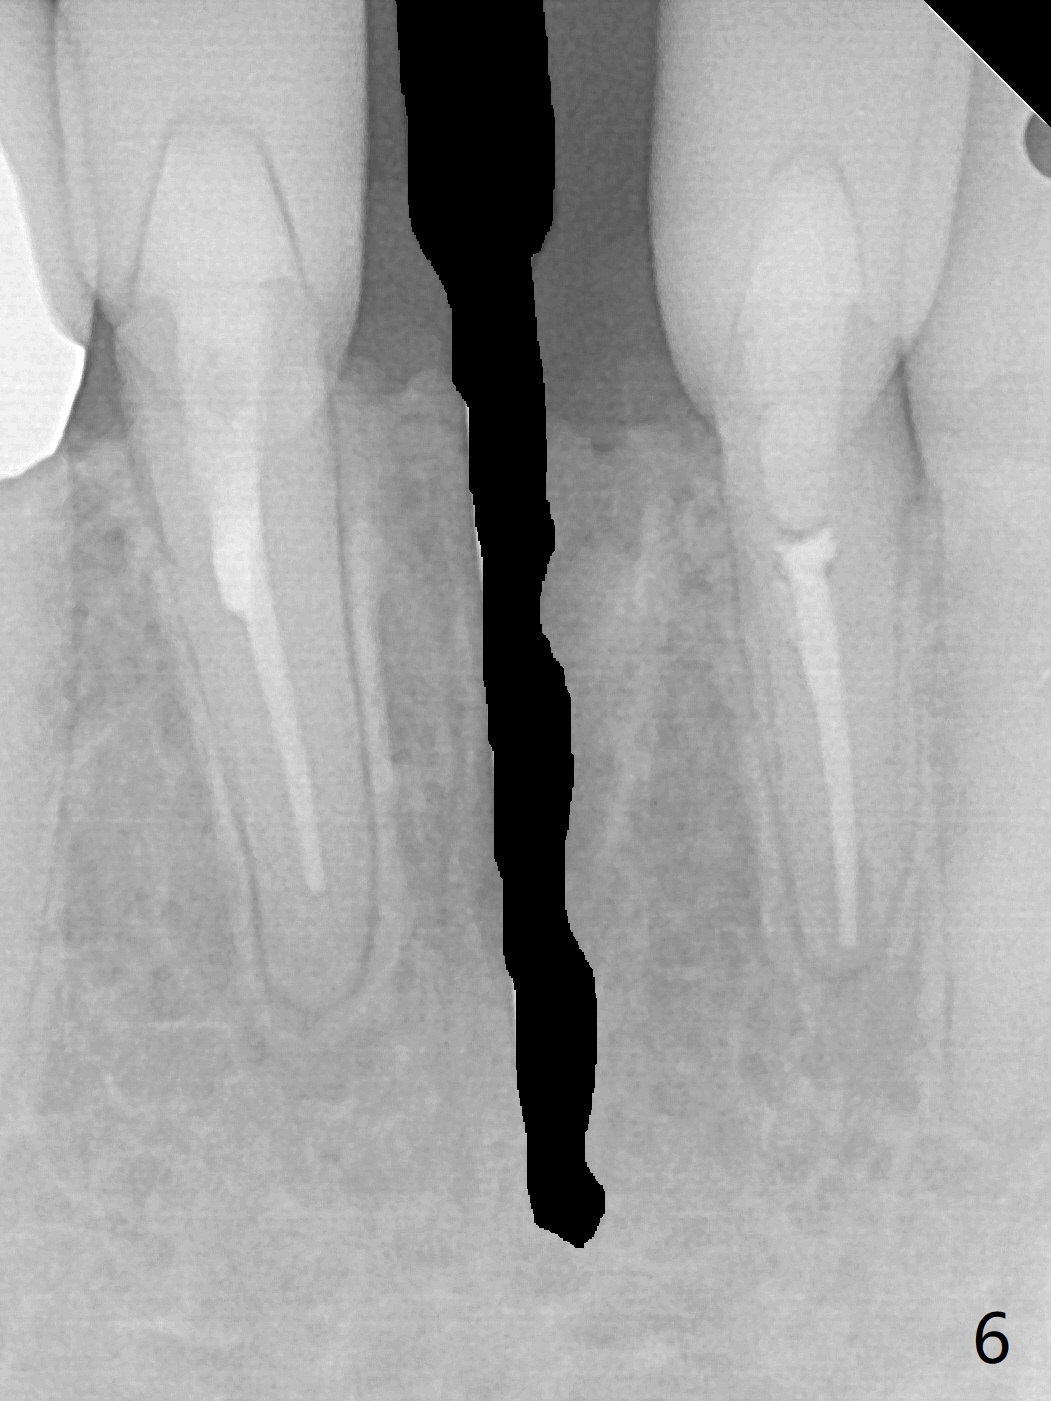

A drawback of implant planning at #25 is not to use a preop PA (Fig.1 (^ fracture line)). The initial trajectory seems to be alright (Fig.2), but a 2.5x14(2) mm implant placed is close to the tooth #26 (Fig.3). In fact the affected tooth is deviated distal; osteotomy should be initiated in the mesial slope of the socket (Fig.4 red line). The final trajectory appears to be perfect (Fig.5). Furthermore the 1st intraop PA should be analyzed carefully (Fig.6). A new osteotomy should be established mesial or the existing one should be moved mesial with Lindamann bur (Fig.7). The distal implant placement may be related to more bone loss in the distal crest 3.5 months postop (Fig.8) and more severe distal papillary recession (Fig.9 *). The bone density increases at the levels of the non-thread and thread portions of the implant (in the original socket) nearly 10 months post cementation (Fig.11 *, <). There is no bone loss 16 months post cementation (Fig.12).